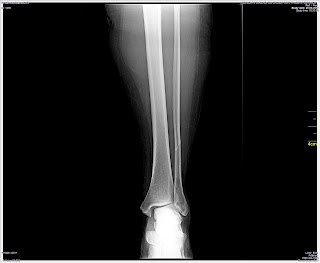

Xrays dated 9 June 2014 taken after the ankle was twisted which show a dislocated ankle.

Xrays taken on 30 July 2014 from an external lab which were shown to Dr Anuj Malhotra at Fortis Hospital on 30 July 2014.